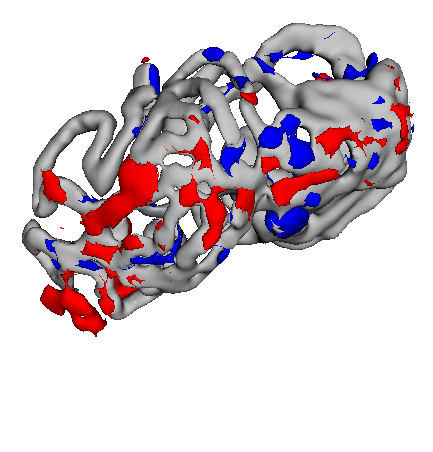

Figure 3 shows example segmentation results in 3D. The result corresponding to ‘feat. & out. level DA’ in Table 1 is compared to ours. We note that the only difference between them is whether the feature disentanglement is involved for the domain adaptation, thus could show its effectiveness. Fewer errors are observed for the proposed method. We believe this is because the proposed method explicitly concentrates on the features more transferable across the datasets, the non-intensity features in this work, by disentangling those features and applying adversarial learning directly to them during the adaptation process. Example reconstruction results from the auto-encoding architecture as well as segmentation results in coronal view can be found in supplementary material.

A

B

B

C

C